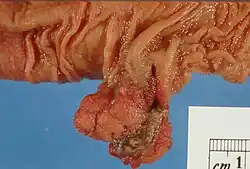

Gross appearance of a colectomy specimen containing two colorectal polyps and one invasive colorectal carcinoma

Gross appearance of a colectomy specimen containing two colorectal polyps and one invasive colorectal carcinoma -